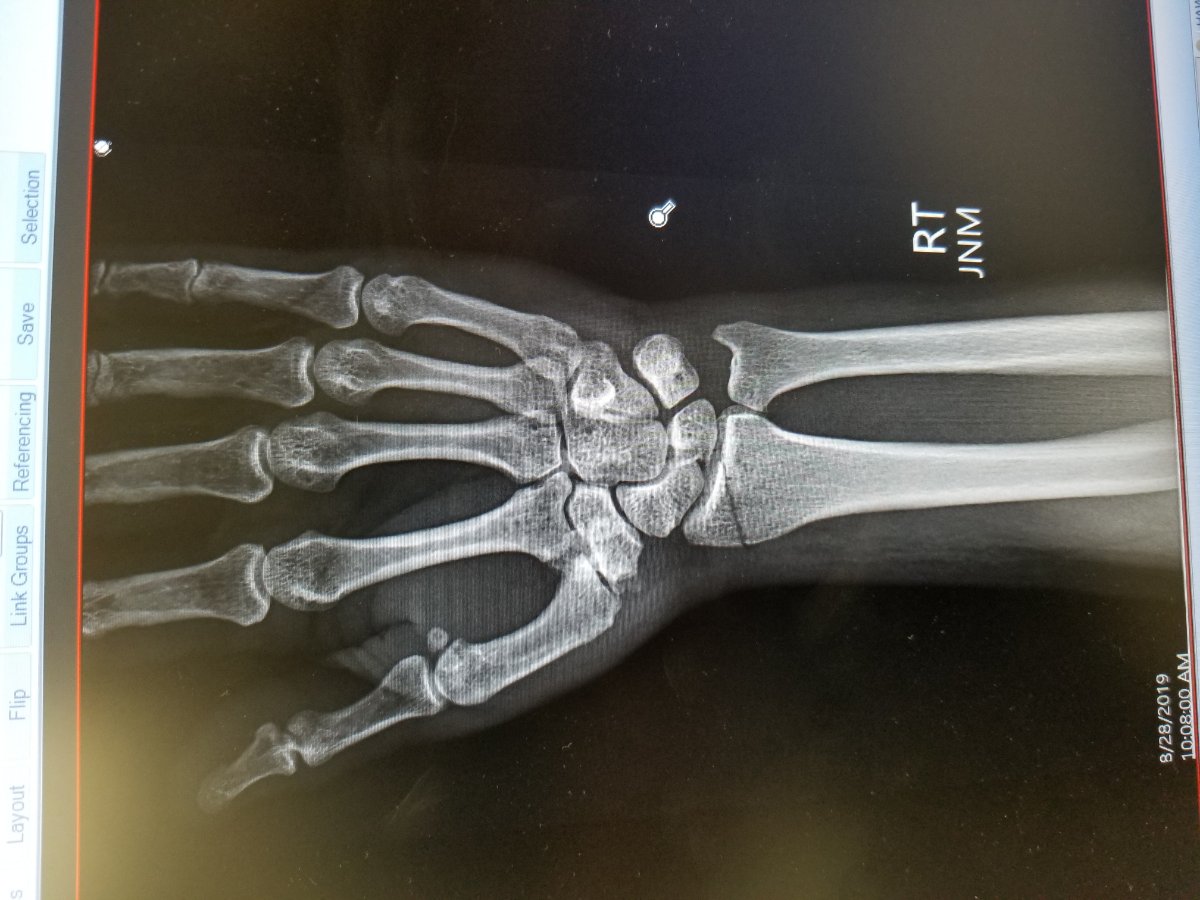

My T broke my wrist DAMN

Sorry for the misfortune. Right hand & wrist?

Right arm near wrist.